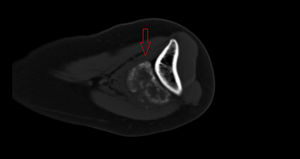

Mujer de 36 años, en seguimiento por tumoración dolorosa y progresiva en cara antero-medial del codo izquierdo e impotencia funcional, de 2 meses de evolución, resistente al tratamiento analgésico. Refería antecedente traumático previo, siendo diagnosticada de rotura fibrilar muscular. Ante la persistencia del cuadro, se realizó RMN ambulatoria, que sospechó un sarcoma de partes blandas, ingresándose para estudio de extensión. Los estudios de laboratorio y TC toraco-abdominal fueron negativos. Mediante gammagrafía ósea en 2 fases (figs. 1A y B), se demostró un área de captación heterogénea en región anterior del codo izquierdo, sin hallazgos significativos a otros niveles. Se planteó diagnóstico diferencial entre sarcoma de partes blandas, condrosarcoma y osteocondroma con degeneración maligna. Finalmente, se decidió biopsia percutánea eco-guiada, cuyo resultado fue de tumoración mesenquimal sin caracteres de malignidad, estableciéndose el diagnóstico definitivo de miositis osificante. Se recomendó reposo, tratamiento antiinflamatorio y rehabilitación posterior. A los 3 meses, presentó mejoría clínica con disminución del dolor, flexión completa y extensión a 120°. El control por radiología simple (figs. 2A y B) y TC sin contraste (fig. 3) reveló una masa calcificada, compatible con el diagnóstico anatomo-patológico.